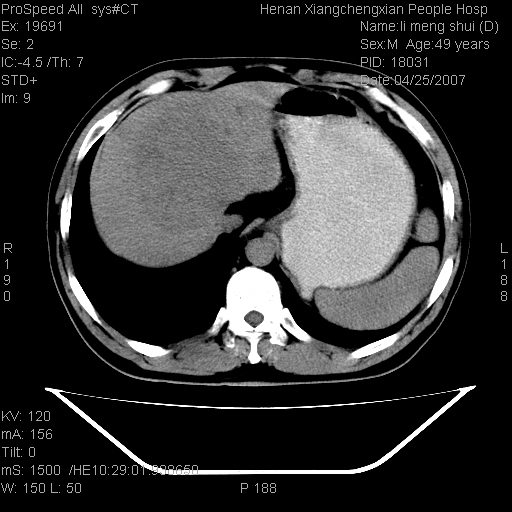

| 患者,男,49岁, 腹疼伴恶心\\呕吐20天,20天前无明显诱因出现右上腹部疼痛,钝疼,无放射,伴恶心\\呕吐,不伴发热.患者不愿增强. b超:肝脏右叶实性占位. ct:肝脏右叶可见一巨块状圆形低密度影,大小约93mm*84mm,其内可见点状高密度影,胆囊、胰腺、脾脏大小、形态及密度未见异常,腹膜后间隙未见肿大淋巴结影。 印象:肝脏右叶巨大肿块,性质待定,建议增强并穿刺活检进一步确诊。 ct平扫: ![]() ![]() ![]() ![]() ![]() ![]() ![]() ![]() ![]() ![]() ![]() ![]() ![]() ![]() ![]() ![]() ![]() 肝脏右叶肿块ct引导下穿刺活检术 患者于16时05分仰卧于ct检查台上,首先行肝脏ct扫描确定进针位置、深度、角度。在局麻下行ct引导下肝脏右叶肿块穿刺活检术。常规消毒、铺巾、局麻。在ct引导下使活检针经右侧腋中线、第9肋间隙垂直胸壁进针90mm,针头进入病变预定位置。在病变预定位置多点、多方向抽取小米样病变组织多块,涂片五张送病理检查。术后穿刺点局部无出血,未出现腹腔积液等并发症。术中及术后患者生命体征稳定,手术于17时10分成功完成。患者安返病房。 穿刺片 ![]() ![]() ![]() ![]() ![]() ![]() ![]() ![]() ![]() ![]() ![]() ![]() ![]() ![]() ![]() ![]() 病理结果肝细胞癌 ![]() 原贴地址:http://www.radinet.com.cn/forum_view.asp?forum_id=4&view_id=24130 ok |